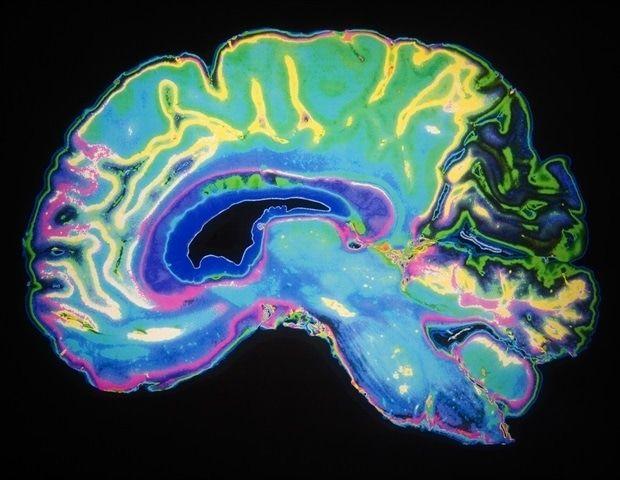

Summary: For the first time, scientists have mapped the genetic architecture of the brain's communication bridge -- the corpus callosum -- using AI and MRI data from over 50,000 people. The study uncovered dozens of genes that shape this vital structure's size and thickness, many active during prenatal development when the brain's wiring is established. Differences in these genes may explain why changes in the corpus callosum are associated with mental and neurological disorders. The team's open-source AI tool now enables global researchers to analyze brain structure faster and with unprecedented precision. For the first time, a research team led by the Mark and Mary Stevens Neuroimaging and Informatics Institute (Stevens INI) at the Keck School of Medicine of USC has mapped the genetic architecture of a crucial part of the human brain known as the corpus callosum -- the thick band of nerve fibers that connects the brain's left and right hemispheres. The findings open new pathways for discoveries about mental illness, neurological disorders and other diseases related to defects in this part of the brain. The corpus callosum is critical for nearly everything the brain does, from coordinating the movement of our limbs in sync to integrating sights and sounds, to higher-order thinking and decision-making. Abnormalities in its shape and size have long been linked to disorders such as ADHD, bipolar disorder, and Parkinson's disease. Until now, the genetic underpinnings of this vital structure remained largely unknown. In the new study, published in Nature Communications, the team analyzed brain scans and genetic data from over 50,000 people, ranging from childhood to late adulthood, with the help of a new tool the team created that leverages artificial intelligence. "We developed an AI tool that finds the corpus callosum in different types of brain MRI scans and automatically takes its measurements," said Shruti P. Gadewar, co-first author of the study and research specialist at the Stevens INI. Using this tool, the researchers identified dozens of genetic regions that influence the size and thickness of the corpus callosum and its subregions. "These findings provide a genetic blueprint for one of the brain's most essential communication pathways," said Ravi R. Bhatt, PhD, co-first author of the study and a post-doctoral scholar at the Stevens INI's Imaging Genetics Center. "By uncovering how specific genes shape the corpus callosum and its subregions, we can start to understand why differences in this structure are linked to various mental health and neurological conditions at a molecular level." The study revealed that different sets of genes govern the area versus the thickness of the corpus callosum -- two features that change across the lifespan and play distinct roles in brain function. Several of the implicated genes are active during prenatal brain development, particularly in processes like cell growth, programmed cell death, and the wiring of nerve fibers across hemispheres. "This work demonstrates the power of using AI and large-scale databases to uncover the genetic factors driving brain development," said Neda Jahanshad, PhD, associate professor of neurology and senior author. "By linking genetics to brain structure, we gain critical insight into the biological pathways that may underlie psychiatric and neurological diseases." Notably, the study found genetic overlap between the corpus callosum and the cerebral cortex -- the outer layer of the brain responsible for memory, attention, and language -- as well as with conditions such as ADHD and bipolar disorder. "These connections underscore that the same genetic factors shaping the brain's communication bridge may also contribute to vulnerabilities for certain disorders," Jahanshad added. Arthur W. Toga, PhD, director of the Stevens INI, emphasized the broader implications of this research. "This study is a landmark in understanding how our brains are built. It not only sheds light on normal brain development but also helps us identify new avenues for diagnosing and potentially treating disorders that affect millions worldwide." The researchers have made their new AI-based tool publicly available to accelerate future discoveries. The software, developed at the Stevens INI, uses advanced machine learning to identify and measure the corpus callosum from MRI scans automatically. This approach allows scientists to analyze brain structure at an unprecedented scale and level of precision, reducing years of manual work to just hours. The Stevens INI has become a global leader in applying artificial intelligence to neuroscience, developing tools that are freely shared with the research community. By combining massive datasets with cutting-edge computational methods, the institute is transforming how scientists study brain health and disease. "Artificial intelligence is revolutionizing brain research, and Stevens INI is at the forefront of that revolution," said Toga. "By pioneering AI tools and making them widely available, we're empowering scientists around the world to unlock new discoveries about the brain far faster than ever before." About the study In addition to Bhatt, Gadewar and Jahanshad, the study's other authors include Ankush Shetty, Iyad Ba Gari, Elizabeth Haddad,Shayan Javid, Abhinaav Ramesh, Elnaz Nourollahimoghadam, Alyssa H. Zhu, Christiaan de Leeuw,Paul M. Thompson,and Sarah E. Medland. Funding: This work was supported by the National Institutes of Health (Grant Nos. R01 MH134004 and R01 AG059874 [NJ], National Science Foundation Graduate Research Fellowship Program (Grant No. 2020290241 [RRB], R01 MH126213, R01NS105746, the Adolescent Brain Cognitive Development (ABCD) Study (https://abcdstudy.org), and UK Biobank (Resource Application No. 11559). SEM was supported by NHMRC grants APP1172917 and APP1158127. Research reported in this publication was supported by the Office of the Director, National Institutes of Health under Award Number S10OD032285. The Genetic Architecture of the Human Corpus Callosum and its Subregions The corpus callosum (CC) is the largest set of white matter fibers connecting the two hemispheres of the brain. In humans, it is essential for coordinating sensorimotor responses and performing associative or executive functions. Identifying which genetic variants underpin CC morphometry can provide molecular insights into the CC's role in mediating cognitive processes. We developed and used an artificial intelligence based tool to extract the midsagittal CC's total and regional area and thickness in two large public datasets. We performed a genome-wide association study (GWAS) meta-analysis of European participants (combined N = 46,685) with generalization to the non-European participants (combined N = 7040). Post-GWAS analyses implicated prenatal intracellular organization and cell growth patterns, and high heritability in regions of open chromatin. Results suggest programmed cell death mediated by the immune system drives the thinning of the posterior body and isthmus. Genetic overlap, and causal genetic liability, between the CC, cerebral cortex features, and neuropsychiatric disorders such as attention-deficit/hyperactivity, bipolar disorders, and Parkinson's disease were identified.

For the first time, a research team led by the Mark and Mary Stevens Neuroimaging and Informatics Institute (Stevens INI) at the Keck School of Medicine of USC has mapped the genetic architecture of a crucial part of the human brain known as the corpus callosum -- the thick band of nerve fibers that connects the brain's left and right hemispheres. The findings open new pathways for discoveries about mental illness, neurological disorders and other diseases related to defects in this part of the brain. The corpus callosum is critical for nearly everything the brain does, from coordinating the movement of our limbs in sync to integrating sights and sounds, to higher-order thinking and decision-making. Abnormalities in its shape and size have long been linked to disorders such as ADHD, bipolar disorder, and Parkinson's disease. Until now, the genetic underpinnings of this vital structure had remained largely unknown. In the new study, published in Nature Communications, the team analyzed brain scans and genetic data from over 50,000 people, ranging from childhood to late adulthood, with the help of a new tool the team created that leverages artificial intelligence. "We developed an AI tool that finds the corpus callosum in different types of brain MRI scans and automatically takes its measurements," said Shruti P. Gadewar, co-first author of the study and research specialist at the Stevens INI. Using this tool, the researchers identified dozens of genetic regions that influence the size and thickness of the corpus callosum and its subregions. "These findings provide a genetic blueprint for one of the brain's most essential communication pathways," said Ravi R. Bhatt, Ph.D., co-first author of the study and a postdoctoral scholar at the Stevens INI's Imaging Genetics Center. "By uncovering how specific genes shape the corpus callosum and its subregions, we can start to understand why differences in this structure are linked to various mental health and neurological conditions at a molecular level." The study revealed that different sets of genes govern the area versus the thickness of the corpus callosum -- two features that change across the lifespan and play distinct roles in brain function. Several of the implicated genes are active during prenatal brain development, particularly in processes like cell growth, programmed cell death, and the wiring of nerve fibers across hemispheres. "This work demonstrates the power of using AI and large-scale databases to uncover the genetic factors driving brain development," said Neda Jahanshad, Ph.D., associate professor of neurology and senior author. "By linking genetics to brain structure, we gain critical insight into the biological pathways that may underlie psychiatric and neurological diseases." Notably, the study found genetic overlap between the corpus callosum and the cerebral cortex -- the outer layer of the brain responsible for memory, attention, and language -- as well as with conditions such as ADHD and bipolar disorder. "These connections underscore that the same genetic factors shaping the brain's communication bridge may also contribute to vulnerabilities for certain disorders," Jahanshad added. Arthur W. Toga, Ph.D., director of the Stevens INI, emphasized the broader implications of this research, stating, "This study is a landmark in understanding how our brains are built. It not only sheds light on normal brain development but also helps us identify new avenues for diagnosing and potentially treating disorders that affect millions worldwide." The researchers have made their new AI-based tool publicly available to accelerate future discoveries. The software, developed at the Stevens INI, uses advanced machine learning to identify and measure the corpus callosum from MRI scans automatically. This approach allows scientists to analyze brain structure at an unprecedented scale and level of precision, reducing years of manual work to just hours. The Stevens INI has become a global leader in applying artificial intelligence to neuroscience, developing tools that are freely shared with the research community. By combining massive datasets with cutting-edge computational methods, the institute is transforming how scientists study brain health and disease. "Artificial intelligence is revolutionizing brain research, and Stevens INI is at the forefront of that revolution," said Toga. "By pioneering AI tools and making them widely available, we're empowering scientists around the world to unlock new discoveries about the brain far faster than ever before."

Researchers at USC have used AI to map the genetic architecture of the corpus callosum for the first time, analyzing data from over 50,000 people. The breakthrough identifies dozens of genes that shape this crucial brain structure and reveals genetic links to mental health disorders like ADHD and bipolar disorder.